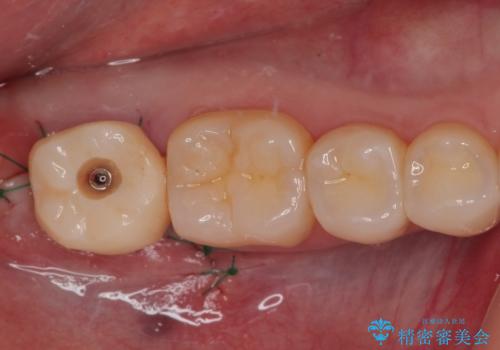

抜歯された骨の穴は、インプラント埋入時にはまだ大きな窩洞となっていましたが、径の大きいワイドインプラントを選択することで、埋入時に十分な安定を獲得することができました。

後方には欠損が残っていたため、補填材を填入しました。

術後にインプラントが骨から脱落することがありますが、特筆するトラブルなどなく、最短の3ヶ月で治療を終えることができました。